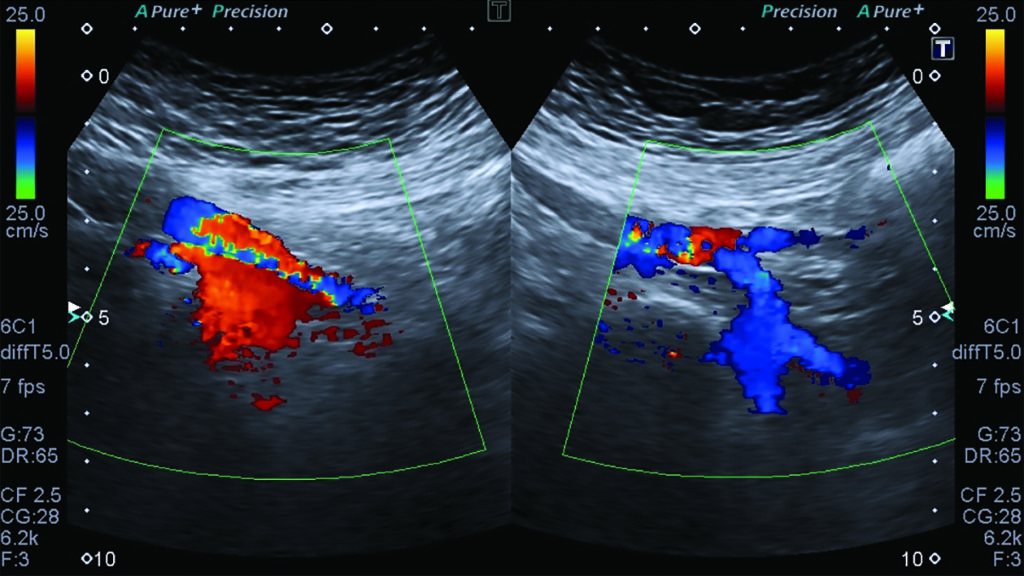

Fig. 7. Doppler color de venas iliacas internas, demostrando flujo reverso del lado izquierdo como signo indirecto de compresión en la VICI.

Se evidencia también flujo reverso en la vena iliaca interna izquierda como signo indirecto de compresión de la VICI (Fig. 7).